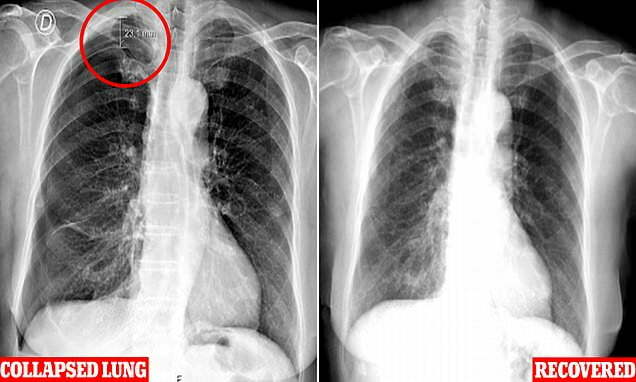

This is evident in the cutting-edge case of a 79-year-old lady from Portugal, currently pronounced via medical doctors from the Centro Hospitalar Universitário de Lisboa Central. The elderly female was first confirmed at the health center with moderate breathing difficulties. An X-ray quickly found the cause – the bottom of her proper lung had been indented using a distance of two. In a condition known as pneumothorax, three centimeters (approximately an inch) is usually called a “collapsed lung”.

In this situation, the needle has been inserted into a space close to the patient’s shoulder blade wherein the lung can come inside centimeters (less than an inch) of the pores and skin floor. Get the attitude and intensity wrong; a needle can pop the hollow pleural space. The female’s remedy required the extremely painful insertion of a chest tube with nearby anesthesia and numerous days of observation at the same time as on oxygen and painkillers. The correct information is she survived the ordeal. As it became her first acupuncture reveal, we wouldn’t be amazed if she would not go to the needles.